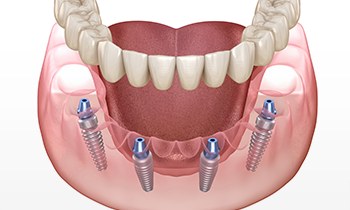

ほとんどの歯を失ってしまったかたを対象に、インプラントを4本または6本埋入し、その上からブリッジを固定する治療方法です。残っている骨を活かしてインプラントを支えとすることで、少ない骨量でも複数の歯を補うことができます。

インプラントと義歯(入れ歯)を組み合わせた治療方法で、歯を失った箇所に2〜4本ほどのインプラントを埋め込み、その上から入れ歯を装着します。インプラントが入れ歯をがっちりと支えるため、通常の入れ歯とは比較にならないほどの安定感と、力強く噛める快適さが手に入ります。より安定感のある入れ歯をお探しのかたにおすすめです。